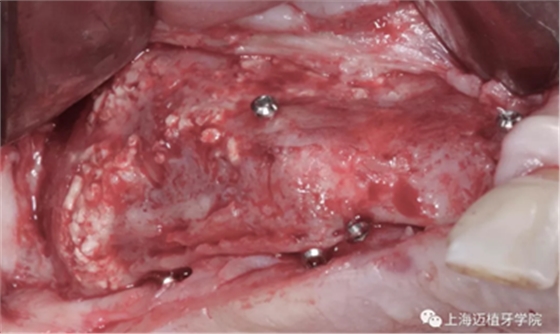

成骨的效果非常好,植入時(shí)可以見(jiàn)血液外滲,血運(yùn)良好